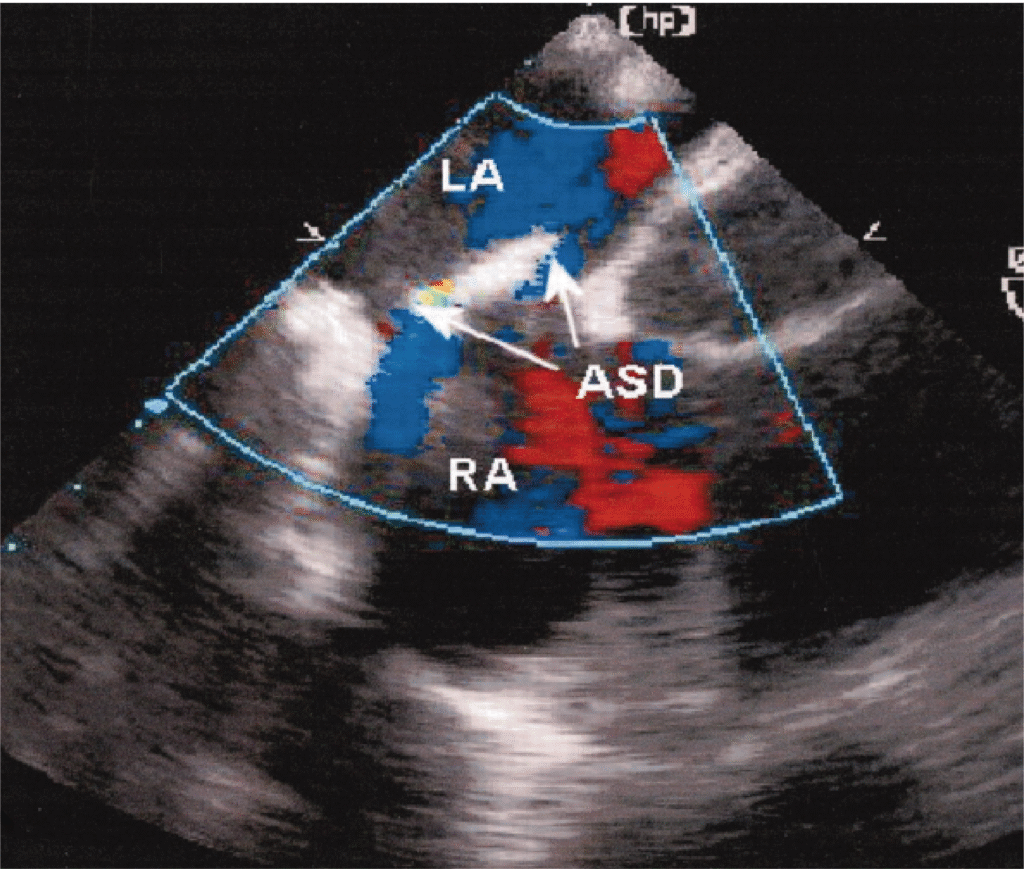

Transthoracic,

Transesophageal And

Intraoperative Echocardiography

Advanced echocardiographic techniques used to assess heart structure and function with unmatched clarity. Whether through the chest wall, esophagus or during surgery, each method delivers critical real-time cardiac insights.